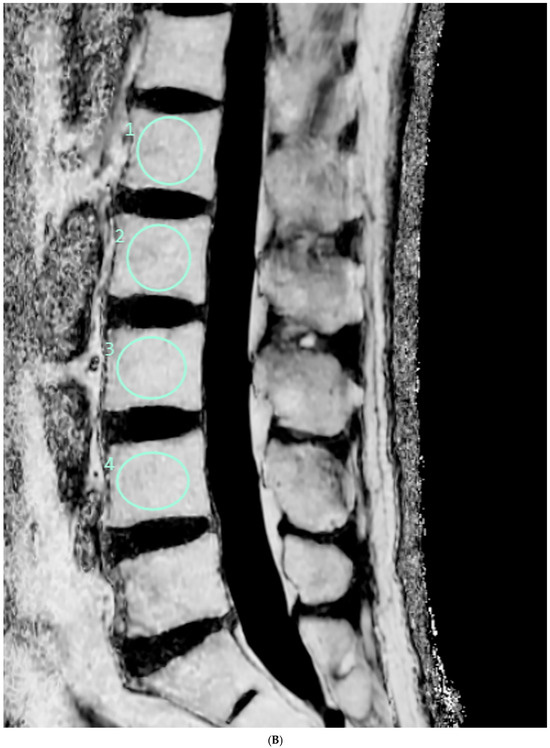

The FF measurement was independently performed by two radiologists who were unaware of the clinical information. Firstly, the FF measurements in GRE-based CSE-MRI were conducted using the INFINITT picture archiving and communication system. Elliptical regions of interest (ROIs) were drawn on the FF map, excluding the posterior venous complex and cortical bone, to encompass cancellous bone as much as possible (Figure 1). ROIs were delineated to the mid-sagittal image. In cases where obtaining information from the central image was challenging, ROIs were drawn on parasagittal images. Measurements were conducted on the L1–L4 bodies, and, in cases where abnormalities invaded all sagittal slices, this level was excluded from the measurements. The median values of the measurements were utilized as representative values (FFGRE). Next, the FF measurement in SE-based CSE-MRI was determined using diffusion analysis software (EXPRESS version 1.0, Philips Healthcare, Seoul, Republic of Korea). This program generates a fat fraction map by simply dividing the signal from the fat-only image by the sum of the signals from the water-only and fat-only images. After creating the FF map using mDixon-XD images, using the same criteria and methodology as in GRE-based CSE-MRI measurements, FF values were obtained from L1–L4 bodies (Figure 1), and the median was used as the representative value (FFSE).

Figure 1.

Lumbar spine MRI of a 59-year-old male. (A) Fat fraction (FF) measurement on gradient-echo (GRE)-based chemical-shift-encoded magnetic resonance imaging (CSE-MRI). The FFGRE in this patient was 66.91%, representing the median value of the L1–L4 vertebral bodies. (B) FF measurement on spin-echo (SE)-based CSE-MRI. The FFSE was 85.84%. The numbers in the figure indicate the ROI numbering in the EXPRESS program. (C) Measurement of the vertebral bone quality (VBQ) score was calculated by dividing the median value of T1-weighted signal of L1–L4 vertebral bodies by the cerebrospinal fluid (CSF) signal at the L3 level. The VBQ score for this patient was 2.63. (D,E) FF color maps were created through GRE- and SE-based CSE-MRI.